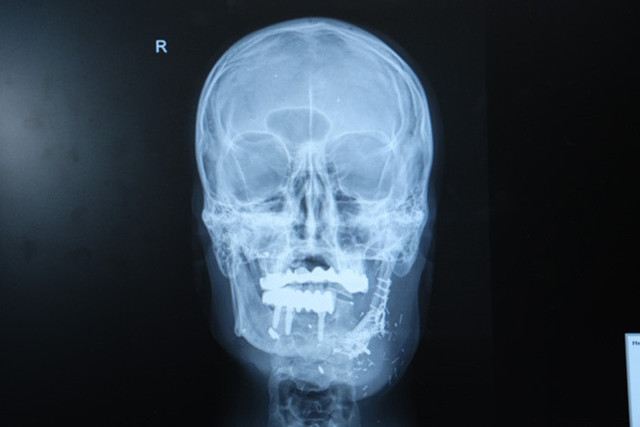

Geçirdiği süreci anlatan İzzet Baldır, “Yoğun bir yaralanmam vardı, birçok hastaneye gittim ve başarısız ameliyatlar geçirdim. Sonunda Dr. Burak Özkan hocamızla tanıştım. Kendisi çok mütevazı ve profesyonel bir insan. Bana sadece bir doktor gibi değil, adeta bir kardeşi gibi davrandı. İlk operasyonda çenedeki eski plaklar çıkarıldı, kemik temizlendi. Bacaktan alınan kemik çeneme nakledildi. Üç ayı geride bıraktık, çok başarılı bir ameliyat oldu. Medipol Mega Hastanesi’nde gördüğüm ilgiden çok memnunum” dedi.

Hastanın durumunun oldukça komplike olduğunu dile getiren Doç. Dr. Özkan, “Hastamız ateşli silah yaralanması sonrası çenesinin yarısını kaybetmişti. Daha önce farklı merkezlerde ameliyat olmuş fakat nakiller başarısız olmuştu. Hem çene bütünlüğünü sağlamak hem de ileride implant yapılabilecek sağlam bir kemik dokusu oluşturmak gerekiyordu. Hastanın bacağından aldığımız kemiği mikrocerrahi yöntemle çeneye naklettik. Damarlara bağlantı yaptık, plaklarla sabitledik. Bu sayede hem fonksiyonel hem de estetik olarak başarılı bir sonuç elde ettik” diye konuştu.

Doç. Dr. Özkan, bu tür vakalarda mikrocerrahinin önemine dikkat çekerek, “Kompozit doku eksikliklerinde vasküler kemik transferi bize büyük avantaj sağlıyor. Hastamız şu an kendi beslenmesini sağlayabiliyor. Önümüzdeki süreçte kemik iyileşmesini tamamladıktan sonra diş implantları yerleştireceğiz ve hastamız çok daha rahat beslenebilecek” şeklinde konuştu.